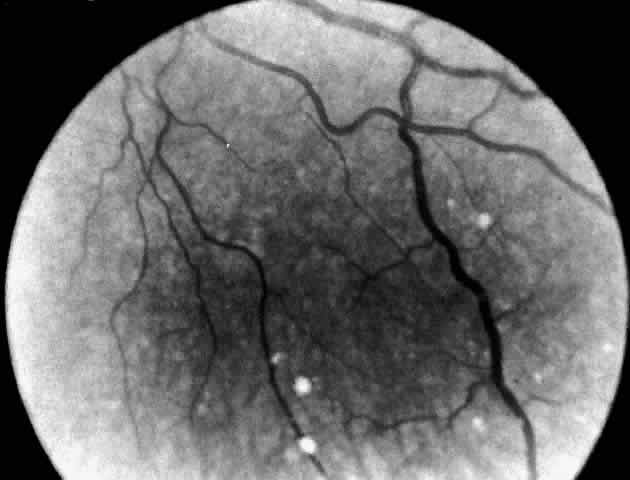

Niemann-Pick Disease Type B. A unique retinal abnormality, the macular halo syndrome has been reported in seven cases of Niemann-Pick disease type B, three enzymatically proven52–54 and four prior to enzyme verification described between 1950 and 1970.55–58 Symmetrical punctate crystalloid ring-form opacities about the foveas were observed in each case with no visual impairment. Cogan and Federman56 in one of the early cases were the first to publish a fundus photograph of the macular halo (Fig. 6). The patient was a 24-year-old woman with hepatomegaly, no neurologic signs, and a reticuloendotheliosis of unclassified type. Both fundi showed doughnut-shaped opacities about the foveas. The opacities were described as yellowish white scintillating granules forming a relatively sharp border on the inner edge of the ring and a ragged border on the outer edge of the ring. Despite this condition the patient had normal visual acuity (20/15 [6/5]) and no scotoma.

Fig. 6. Fundus of patient with Niemann-Pick disease type B showing the macular halo syndrome. (Cogan DG, Chu FC, Barranger JA, Gregg RE: Macular halo syndrome; variant of Niemann-Pick disease. Arch Ophthalmol 101:1698, 1983. Copyright © 1983, American Medical Association)

Although these scattered reports were in the literature, it was Cogan who clearly identified the lesion and made the association with Niemann-Pick disease type B. Cogan and co-workers53 reexamined their initial patient and added a 21-year-old man with a history of splenomegaly and hyperlipidemia. The diagnosis of Niemann-Pick type B disease in each of these patients was confirmed by finding significantly lower sphingomyelinase levels in cultured skin fibroblasts. They named the condition macular halo syndrome. In these cases, the opacities in the retina formed a halo approximately one-half disc diameter at their outer edge. The halo had a crystalloid appearance. By stereo-ophthalmoscopy, slit lamp biomicroscopy, and fluoroangiography the opacities appeared to occupy various depths of the retina but were most numerous in Henle's fiber layer, causing only minor obscuration of the overlying vessels.

The foveal lesion in Matthews and associates' patient54 is similar in size and appearance to the fundus photograph published by Cogan and coworkers. On the basis of stereo biomicroscopy and contact lens examination, Matthews and associates located the lesion in the ganglion cell layer of the retina. The masking effect that the ring lesion had on the perifoveal vasculature in the early fluorescence angiogram was taken as confirmation that the accumulated material is in this superficial layer of the retina. As a result, Matthews and associates proposed that the macular halo represents the smallest or mildest form of a cherry-red spot—findings in conflict with those of Cogan. The precise location of the opacities in the retina remains uncertain, however, because of the lack of histopathology.

The available clinical data suggest that such opacities are permanent. For example, the appearance of the macular halo remained unchanged for 15 months in one case,57 4 years in another,52 and more than 20 years in one of Cogan's cases.53 Cogan concluded that the remarkable preservation of normal visual function in all of the cases either was due to hiatuses in the opacities or, less likely, to a localization of the opacities behind the photoreceptors.